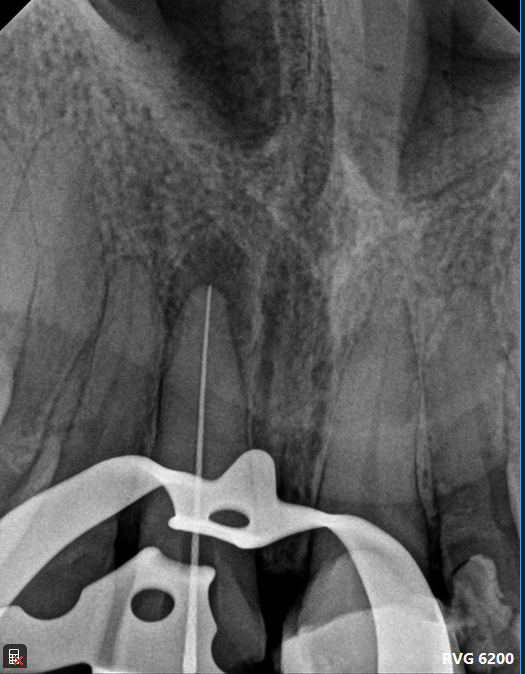

Case: RCT on Tooth #9

31-year-old male, healthy, no medications, no known allergies.

CC: Pain and swelling

Dx: Pulp necrosis and acute apical abscess (#9).

Extraoral: Upper lip fullness and tenderness.

Intraoral: Swelling and localized abscess.

Tx: Two-visit non-surgical root canal therapy with incision and drainage.

Reflection

This case involved managing both endodontic infection and acute swelling. The presence of facial swelling emphasized the urgency of drainage and systemic management. Coordinating I&D with RCT and pharmacologic support reinforced the value of staged treatment for optimal healing.